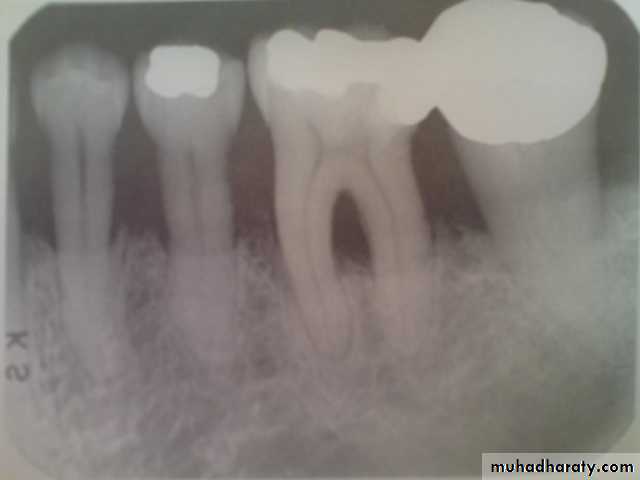

SEVERITY:

slightly, moderate ,or severe.Severity is measured by clinical attachment loss (CAL).

CAL is a measurement of the distance in mm from CEJ to the base of the sulcus or periodontal pocket: CAL is measured by calibrated periodontal probe.

- slightly bone loss: 1 to 2mm

- moderate bone loss: 3to 4mm- severe bone loss: 5mm or greater

slightly

moderate

severe